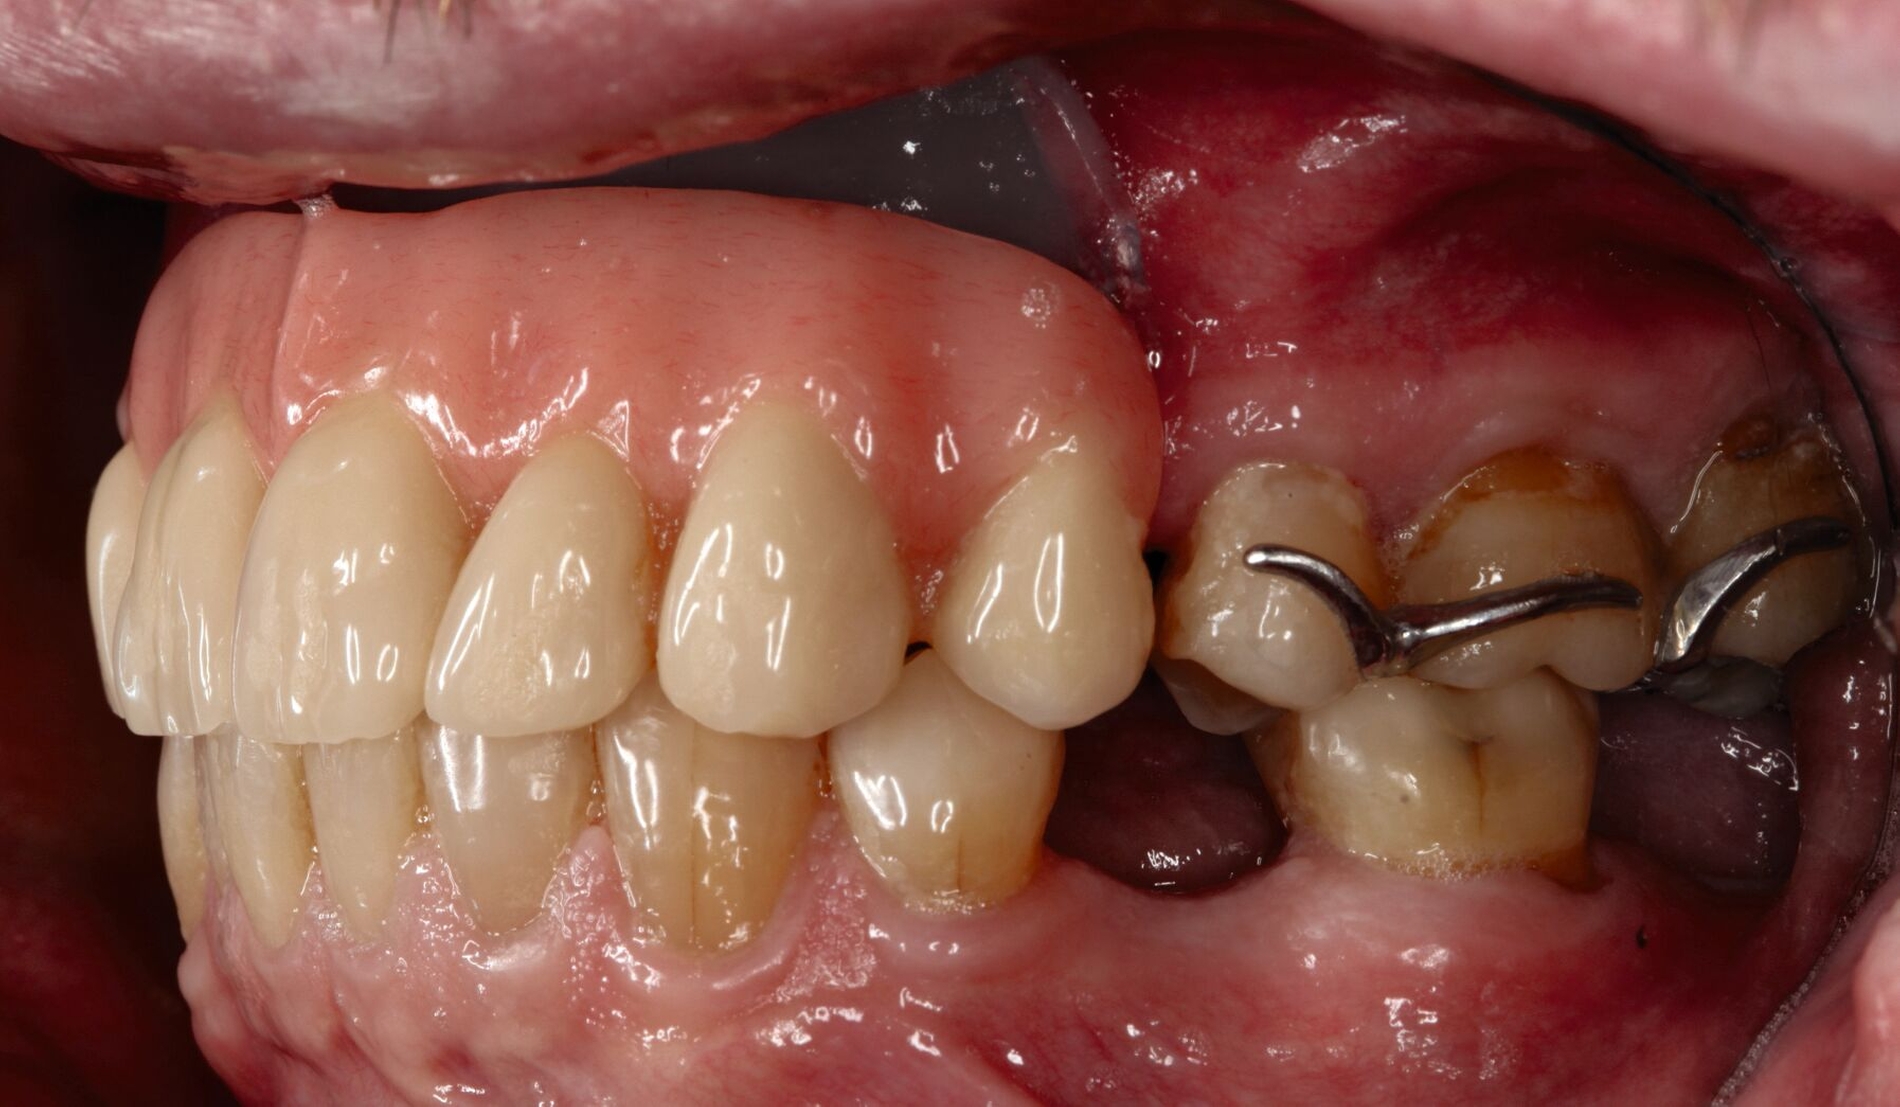

Bei der Tumornachsorge zeigt sich ein großer Vorteil des prothetischen Defektverschlusses: Zusätzlich zur Bildgebung kann mithilfe klinischer Inspektion frühzeitig ein Rezidiv entdeckt werden [Ali et al., 1995; Moreno et al., 2010]. Beim prothetischen Defektverschluss kann eine Acrylat-Obturator-Prothese gewählt werden, die je nach Mundöffnung ein- oder mehrteilig gestaltet ist und die auch verlorengegangene Zähne ersetzt. Alternativ gibt es die zwingend zweiteilige Möglichkeit eines Defektverschlusses über einen Silikon-Obturator mit einer darauf sitzenden Prothese zum Ersatz von Zähnen.

Ein Silikon-Obturator (Abbildung 1) wird über „unter-sich-gehende“ Bereiche im Defekt verankert, kann hohl oder massiv gestaltet sein und sollte im Mund über einen fein auslaufenden Rand (Federrand) am restlichen Weichgewebe enden. Durch diesen feinen Rand ist die Abdichtung zur Nase wie mit einem Saugstopfen sehr gut. Bei fehlendem Vestibulum ist ein fein auslaufender Rand technisch nicht möglich, weshalb durch einen Silikon-Obturator hier nur in seltenen Fällen ein zufriedenstellender Halt erreicht wird. Optimalerweise sollte der Silikon-Obturator täglich vom Patienten entfernt und gereinigt werden können, um die Ansiedlung von Pilzen zu vermeiden.